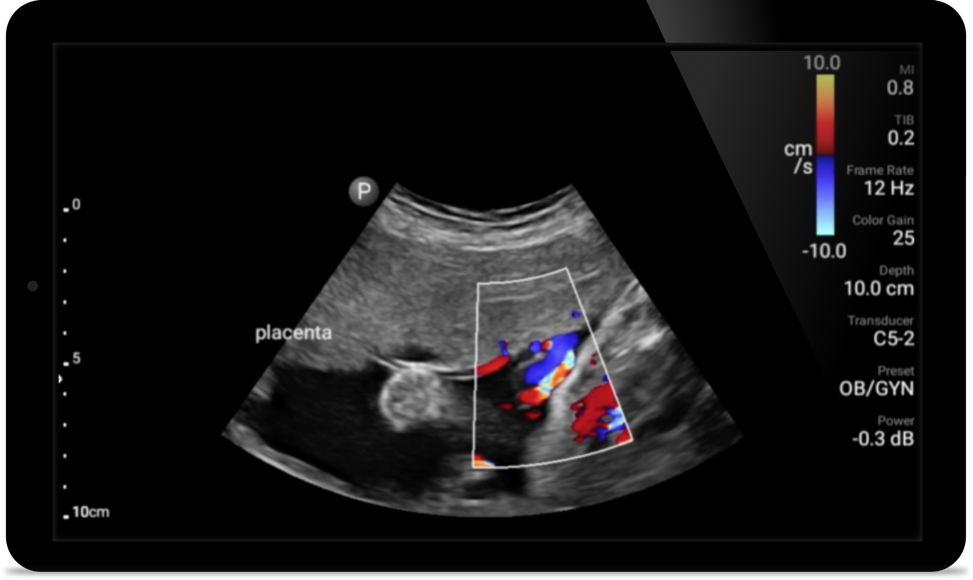

Case study

Opportunity to potentially reverse cardiomyopathy